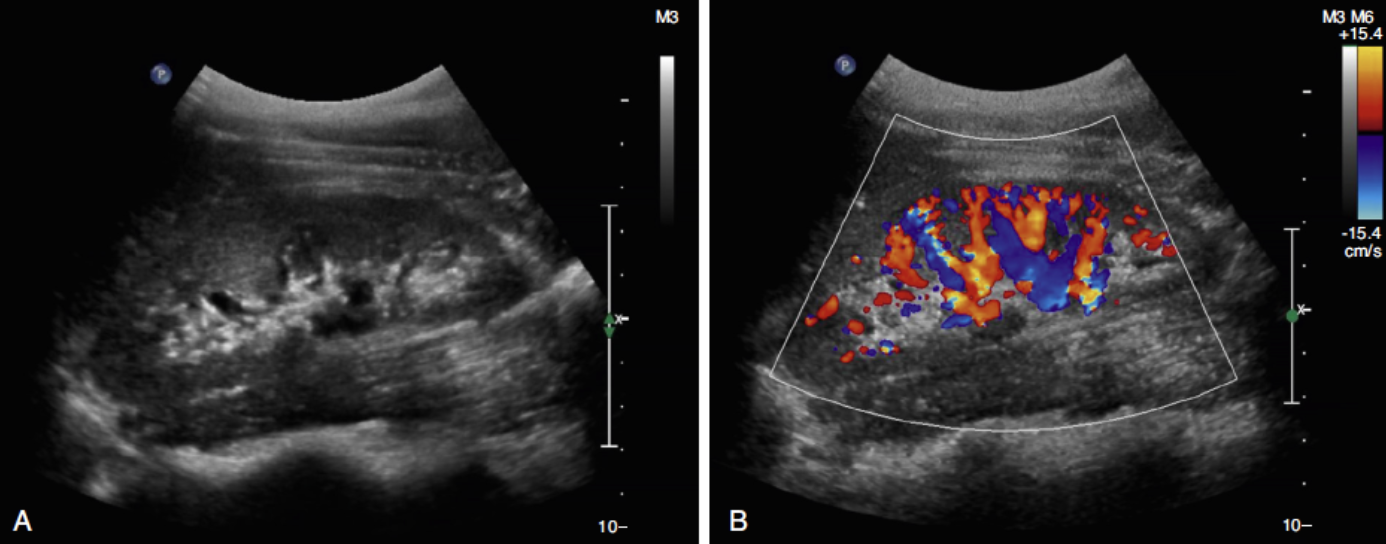

US

Hidronefrosis